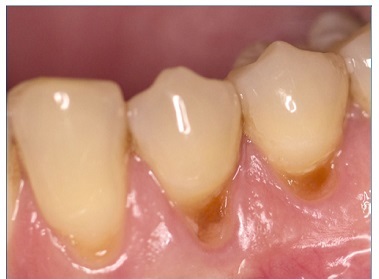

There were no dropouts in this study, so all patients were evaluated at baseline and at 6 months. Representative images of restorations are presented in Figures 1, 2, 3, 4, 5, and 6.

Figure 4 Photographs after 6 months of tooth 44’s restoration by the self‑etch technique and tooth 45’s restoration by the etch‑and‑rinse technique